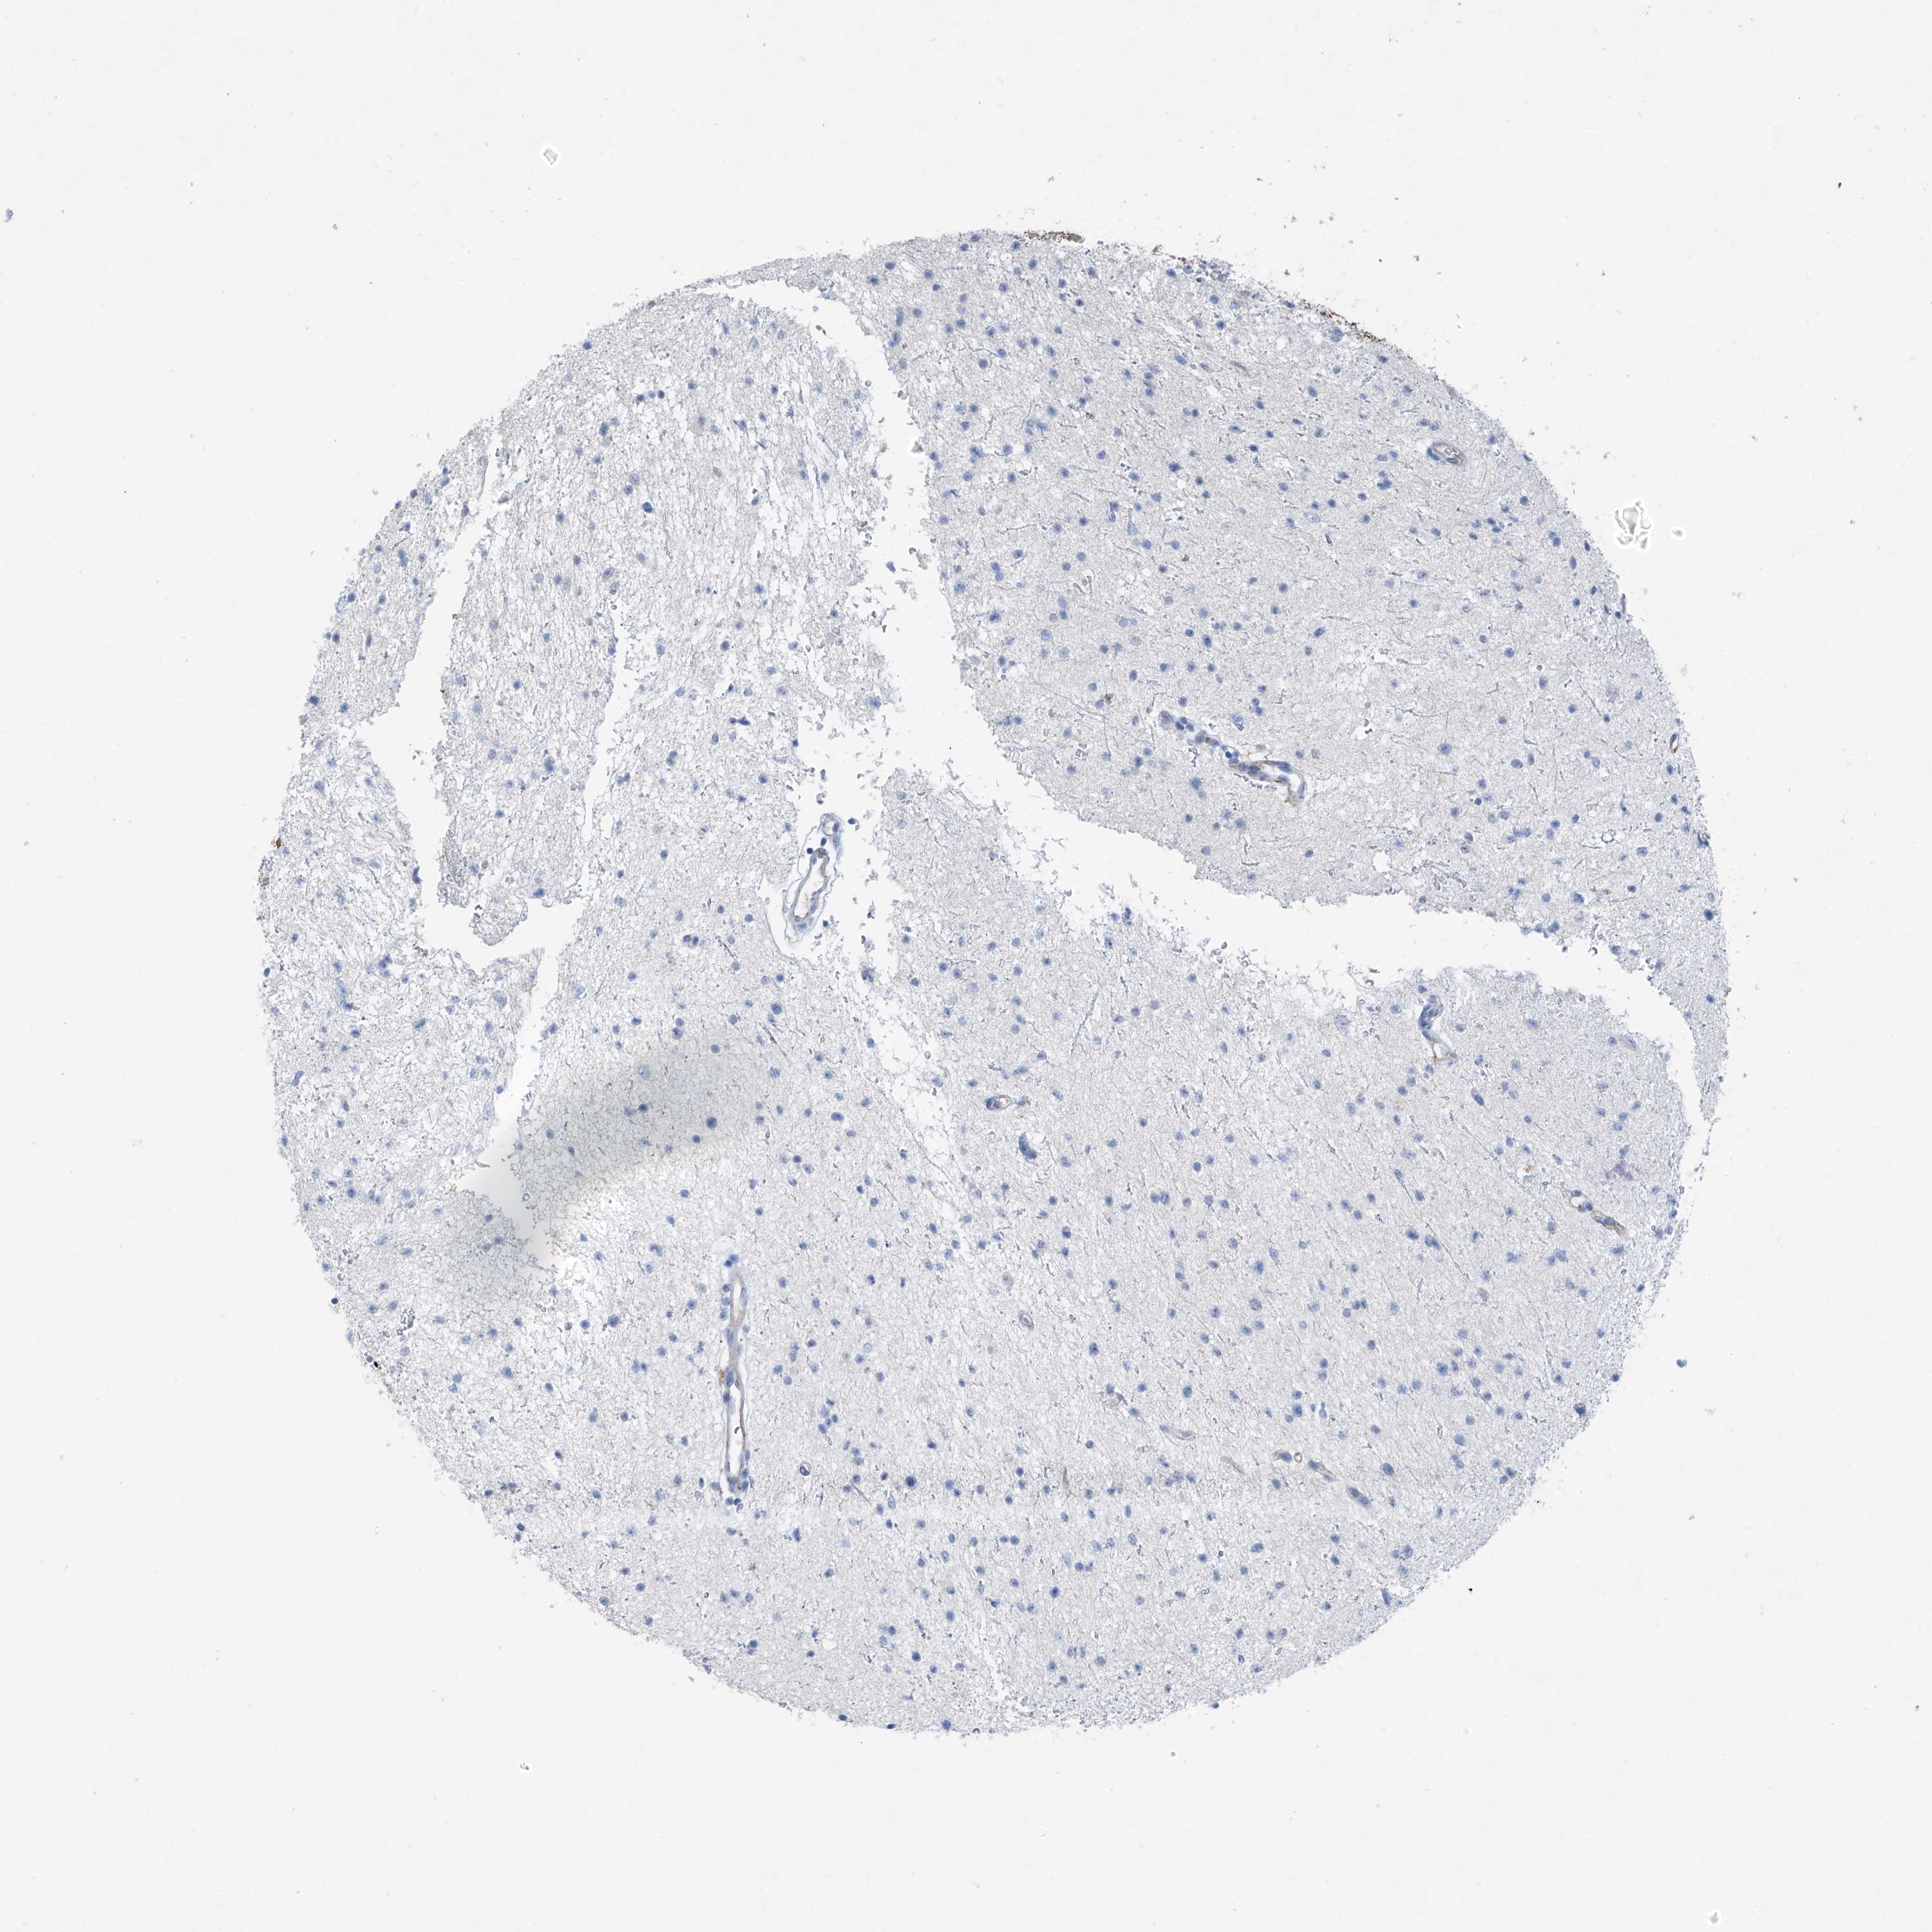

GLIOMA - Protein expressioni

A mouse-over function shows sample information and annotation data. Click on an image to view it in a full screen mode. Samples can be filtered based on level of antibody staining by selecting one or several of the following categories: high, medium, low and not detected. The assay and annotation is described here.

Note that samples used for immunohistochemistry by the Human Protein Atlas do not correspond to samples in the TCGA dataset.

Antibody stainingi

Antibody staining in the annotated cell types in the current human tissue is reported as not detected, low, medium, or high, based on conventional immunohistochemistry profiling in selected tissues. This score is based on the combination of the staining intensity and fraction of stained cells.

Each image is clickable and will lead to virtual microscopy that enables deeper exploration of all samples and also displays staining intensity scores, fraction scores and subcellular localization as well as patient and tissue information for each sample.

Antibody HPA009134

Staining

High

Medium

Low

Not detected

Intensity

Strong

Moderate

Weak

Negative

Quantity

>75%

75%-25%

<25%

None

Location

Nuclear

Cytoplasmic/membranous

Cytoplasmic/membranous,nuclear

Glioma, malignant, High grade

Glioma, malignant, Low grade

Glioblastoma, NOS